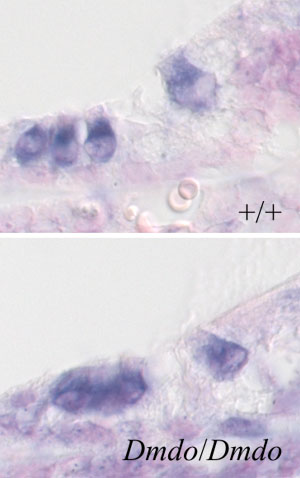

In the mouse, the precise role of the mutation can be examined. Mutation of the miR-96 gene seemed to disrupt development of intricate sensory hair cells in the mutant mice. Mice with two copies of the mutant gene had malformed hair cells from birth and the cells degenerated from an early age. In mice with one copy of the mutant gene, the effects were less severe, but became worse with age.